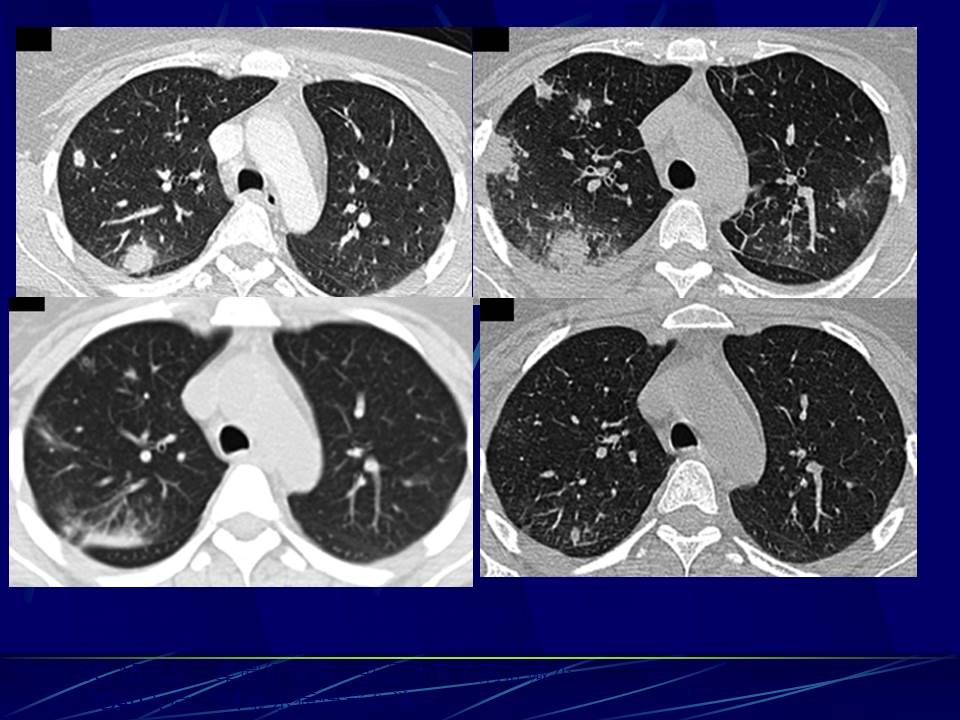

肺部真菌感染影像学分析